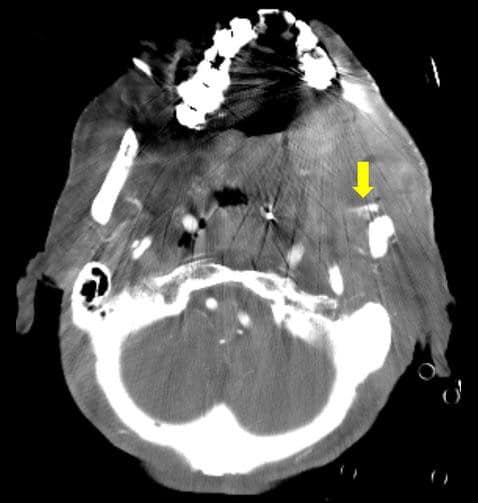

左顎下の術後部位に再発腫瘍が疑われたが、iMARなしの画像では診断が困難であった。iMARありの画像では造影剤のリークが明瞭になり、診断確定が可能になった。その後、血管塞栓術が施行され、顎動脈を選択し、コイルにて止血術が行われた。出血コントロールは良好であったが、蘇生後低酸素脳症があり、脳機能回復が見込めなかったため、12日後に死亡退院。

CT技術や撮像プロトコル設定について

本症例のような術後の場合、手術に伴う金属のメタルアーチファクトが診断の障害になることが多い。フォトンカウンティングCTではメタルアーチファクト低減アプリケーションがあり、撮影後に後処理にてメタルアーチファクトを低減することができ、撮影された画像をみて、必要に応じて、メタルアーチファクトを減らすことが可能となっている。本症例でも造影剤のリークが不明瞭であったため、メタルアーチファクトを低減することで、造影剤のリークを検出することが可能となった。